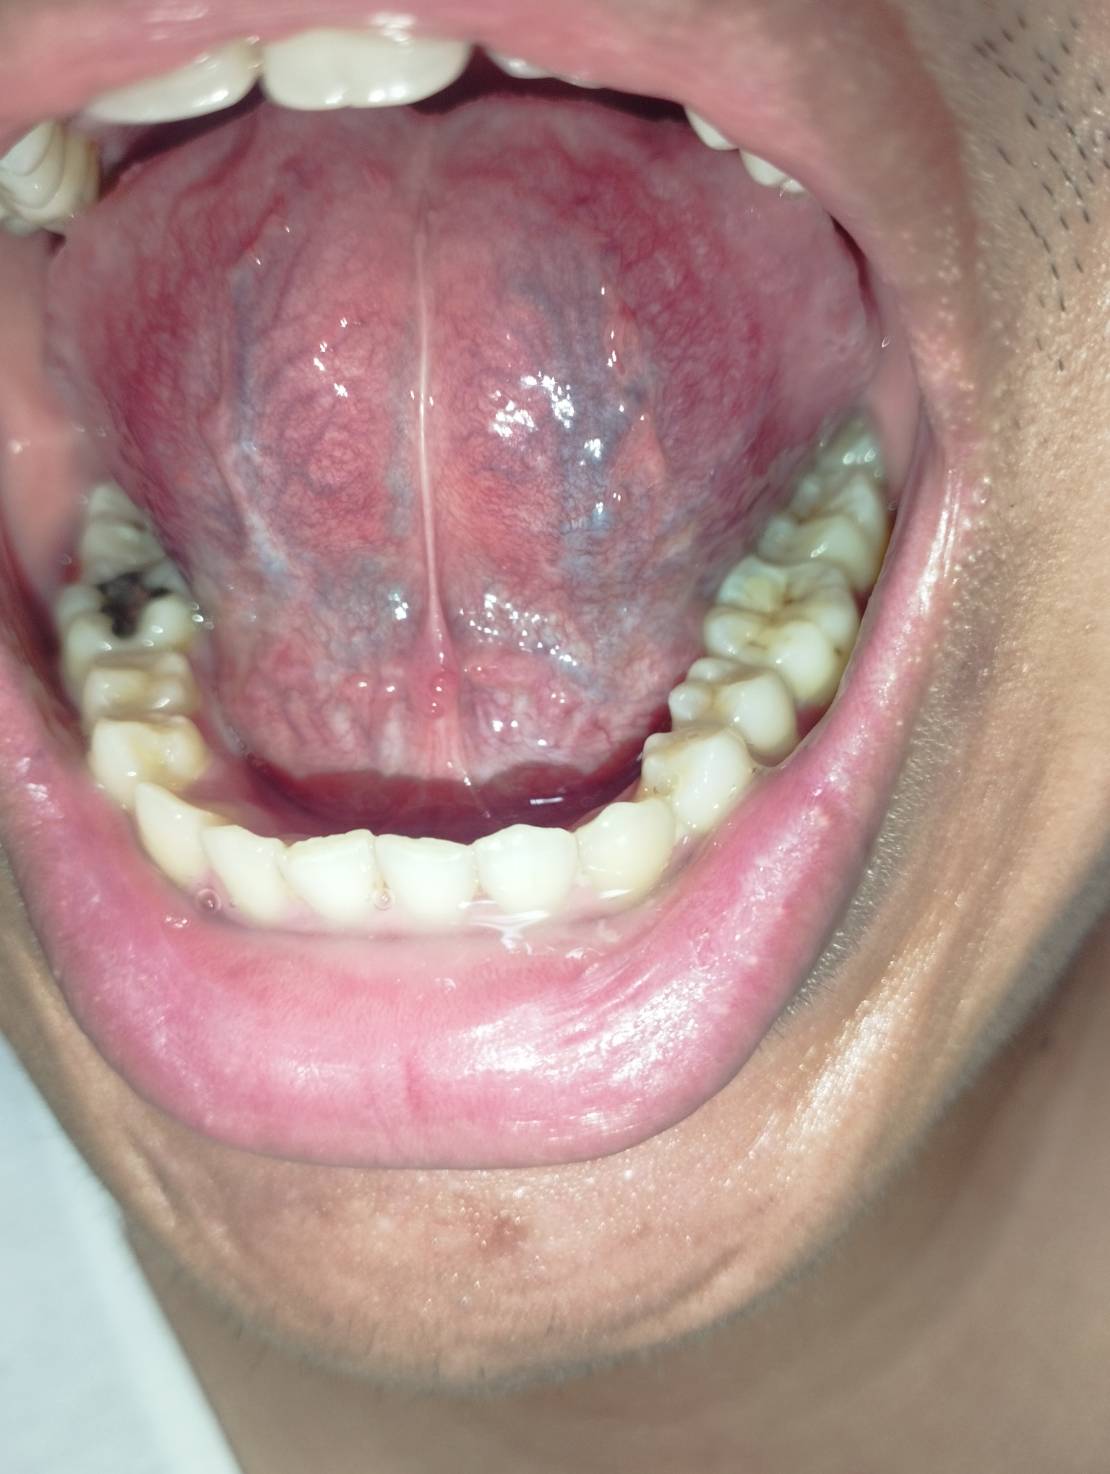

19 เมษายน 2568 10:40:50 #1 https://haamor.com/media/create_topic/20250419103126.jpg https://haamor.com/media/create_topic/202504191031261.jpg https://haamor.com/media/create_topic/202504191031262.jpg https://haamor.com/media/create_topic/202504191031263.jpg ไม่มีอาการเจ็บ หรือปวดครับ ผมเพิ่งสังเกตุเห็นครับ ผมเคยเป็นหูดบริเวณทวารเมื่อช่วงเดือนพฤศจิกายน 2567 ซึ่งรักษาหายช่วงเดือนกุมภาพันธ์ครับ หลังจากเกิดเหตุนั้นมา ผมยังไม่เคยไปมีเพศสัมพันธ์ |

21 เมษายน 2568 20:20:52 #2 ปกติครับ ลองไปขอดูเพื่อนๆหลายๆคนครับ สบายใจได้ครับ |